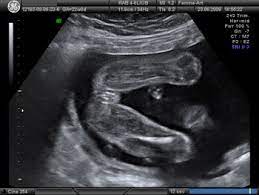

Chłopiec czy jednak dziewczynka ?

No właśnie tu ich nie ma. Jak jest USG dziewczynki, to tam pomiędzy nogami zarysowuje się taki hamburgerek.

Zdjęcie z netu - widzisz takie kreseczki pomiędzy nogami?

indeks.jpg

7,1 KB · Wyświetleń: 377